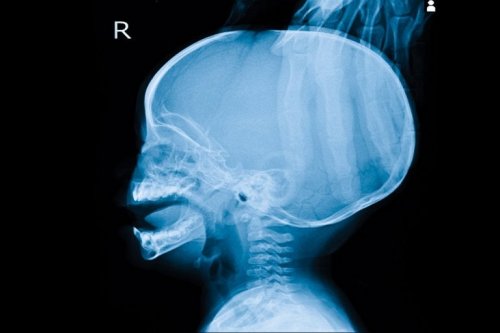

Hidrocefalia

A hidrocefalia é o acúmulo de líquido nas cavidades profundas do sistema nervoso central. Em suma, este líquido comprime o encéfalo. À primeira vista, pode ser percebida pelo tamanho aumentado da cabeça do neonato.

Além disso, pode produzir sintomas variados, desde vômitos até sonolência e irritabilidade ou convulsões.